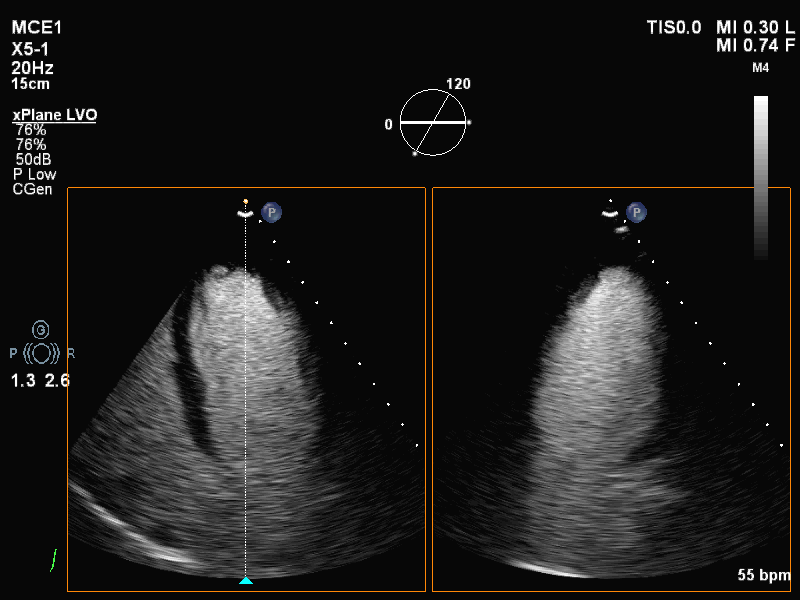

动态图(2)静息状态双平面LVO

动态图(3)静息状态左室长轴图

负荷前左室壁未见明确节段性运动异常,左室各节段心肌灌注充盈良好。

平板负荷量达89%时,该时患者心率157次/分,出现短阵性室性心动过速,即刻超声造影检查显示:负荷后左室前间隔中段、室间隔心尖段、侧壁中段、心尖段、下壁心尖段、前壁心尖段及心尖帽运动减弱。室间隔心尖段及心尖帽心肌灌注稀疏。

患者休息后检查:左室壁未见明确节段性运动异常,左室各节段心肌灌注充盈良好。